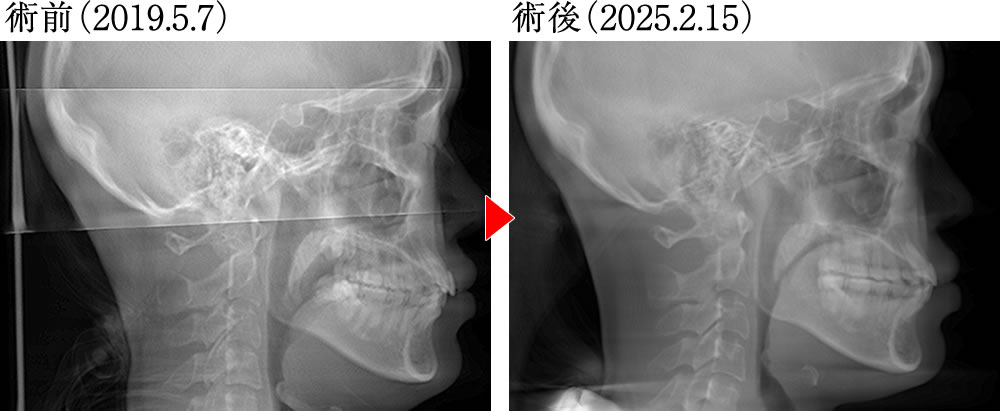

術前術後の骨格の変化

術前は下顎前歯が乱れつつ内側へ傾斜しており、歯列も狭かったため、舌や舌骨が低い位置にありました。しかし術後は前歯が理想的な被蓋関係となり、歯列も拡大されたことで十分な舌スペースが確保されました。その結果、舌は上顎口蓋にしっかり接し、舌骨も大きく上方へ挙上し、理想的で安定した口腔環境が実現しました。